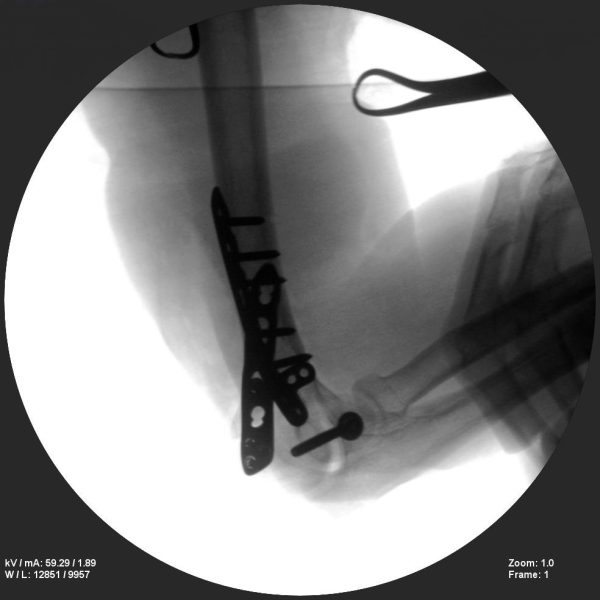

Hip fixation

Skan-C is a great C-arm for orthopaedic treatments for several reasons